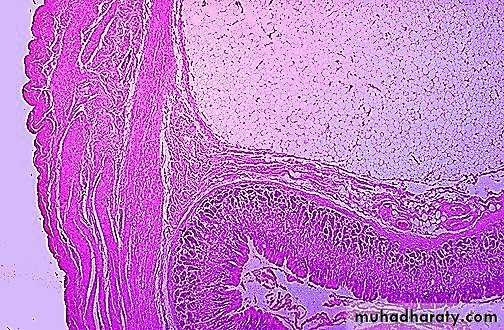

Microscopic examination reveals the lipoma at the upper right to be composed of cells essentially resembling mature adipose tissue. Benign tumors closely resemble the cell of origin.